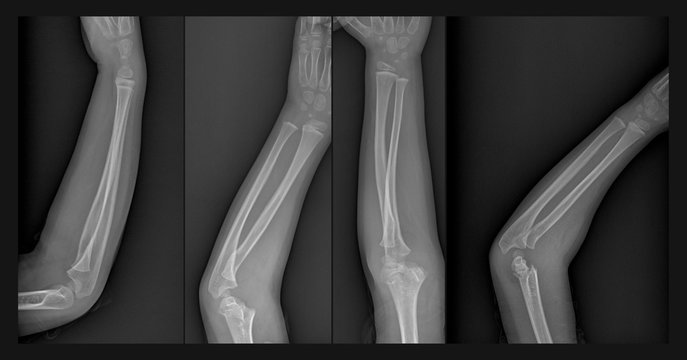

골수염은 빠르게 또는 시간이 지남에 따라 발생할 수 있습니다. 감염은 모든 연령대에서 발생할 수 있습니다. 팔이나 다리를 포함하는 장골 감염은 어린이에게 더 흔합니다. 그러나 일반적으로 고령자는 당뇨병이나 수술이 필요한 정형외과 문제와 같은 감염 위험을 증가시킬 수 있는 건강 문제를 더 많이 경험하기 때문에 골수염에 걸리기 쉽습니다.

비혈액성 골수염은 골절이나 열린 상처와 같은 외상으로 인해 발생할 수 있습니다. 특히 박테리아나 곰팡이를 옮길 수 있는 금속 핀, 나사 또는 판과 같은 보철 재료가 관련된 경우 수술이 원인일 수 있습니다. 소아에서 비혈액성 골수염이 발병하면 외상으로 인한 것일 가능성이 큽니다.

또한, 골수염 진단을 위해서는 엑스레이, MRI, CT 스캔, 뼈 스캔 또는 초음파와 같은 영상 검사를 실시할 수 있는데, 이는 뼈 손상의 정도를 나타낼 수 있습니다.